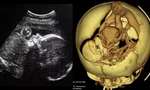

| Bé trai cân nặng đến 5kg |

Nhờ sự phối hợp nhịp nhàng của các y, bác sĩ, sản phụ sinh thường thành công chỉ sau khoảng 10 phút. Một bé trai nặng 5kg đã chào đời một cách ngoạn mục bằng phương pháp sinh thường. Sau sinh, tình trạng của mẹ và bé đều ổn định.

Bác sĩ chuyên khoa 1 Phạm Thanh Nam, Trưởng khoa Sản phụ, Bệnh viện Hoàn Mỹ Bình Phước cho biết, đây là trường hợp sinh thường với bé trai cân nặng hiếm gặp. Theo bác sĩ Nam, thông thường, với những thai nhi có cân nặng lớn được chỉ định sinh mổ vì sản phụ rất dễ bị những di chứng như: băng huyết, rách phần mềm phức tạp, thậm chí vỡ tử cung, thai nhi cũng rất dễ bị tổn thương. Riêng với trường hợp của sản phụ N.T.T.U, các bác sĩ chẩn đoán và tiên lượng có thể sinh thường được.